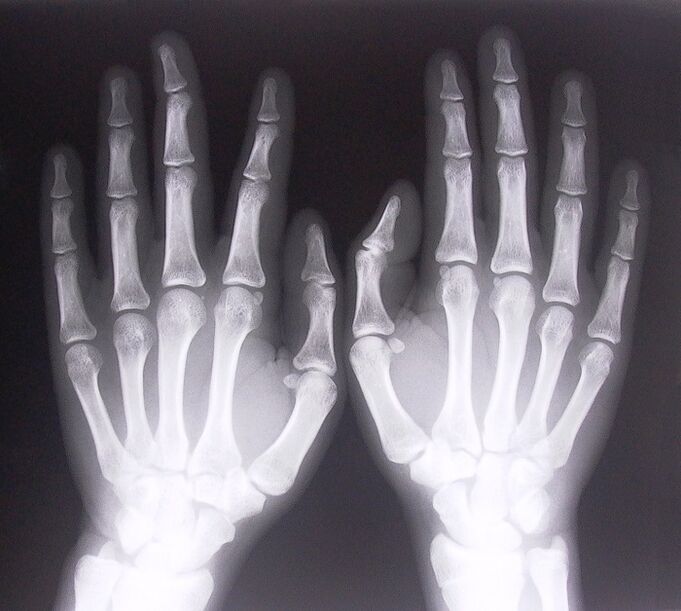

- Stenosing ligamentitis.To identify the cause of the disease, it is necessary to undergo an x-ray.Symptoms are typical: painful movement of the hand, looping of the clenched palm.Also, during extension, clicks are usually heard.

To begin treating joint pain in the fingers, you need to correctly determine what disease caused them.To determine what kind of disease is afflicting a person who feels pain in the joints when bending their arms, doctors recommend undergoing the following procedures:

- Take x-rays.